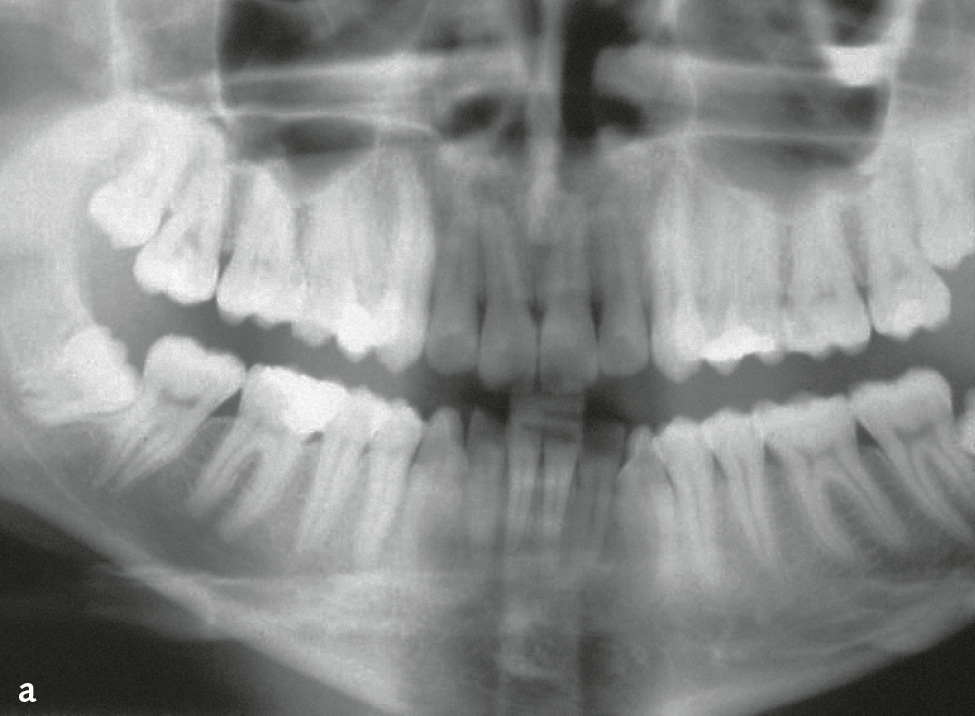

Die Differenzialdiagnose zwischen primär endodontaler Läsion bei partieller Pulpanekrose und tiefer primär parodontaler Läsion, die zu einem Parodontalabszess geführt hat, ist diffizil. Hilfreich ist es, bei der Röntgendiagnostik einen röntgenopaken Stift (z. B. Guttaperchapoint) in die Fistel/parodontale Tasche einzuführen (Abb. 7c, 8). So lässt sich häufig der Ursprung der Eiterung (z. B. periapikale Region) darstellen. Hinweise für eine primär endodontal verursachte Läsion sind kariöse Läsionen (Abb. 8b) oder pulpanahe Restaurationen und Kronen2. Bei etwa 10 % der Kronen kommt es in den ersten 10 Jahren nach Präparation zu Pulpanekrosen. Bei einem Patienten, der generell keine oder wenig Attachmentverluste oder Knochenabbau und nur isoliert an einer Stelle eine stark erhöhte Sondierungstiefe mit Suppuration aufweist (endodontal-parodontale Läsion ohne Beschädigung der Wurzel bei Patienten ohne Parodontitis: Grad 1), sprechen die Befunde für eine primär endodontale Läsion (Abb. 7c, 8). Ein Patient, der auch an anderen Stellen lokalisiert oder generalisiert tiefe Taschen sowie Knochenabbau zeigt, bei dem aber der Beschwerden bereitende Zahn endodontisch nicht vorgeschädigt ist, hat mit hoher Wahrscheinlichkeit eher ein primär parodontales Problem. Eine periapikale hypodense (radiotransluzente) Zone auf zweidimensionalen Röntgenbildern muss kein eindeutiger Hinweis auf eine Läsion primär endodontaler Genese sein. Die dreidimensionale Ausdehnung primär parodontaler Knochentaschen kann je nach Projektion periapikale Osteolysen vortäuschen (Abb. 9).

Abb. 9 Palatinaler Knochendefekt primär parodontalen Ursprungs, dessen apikale Ausdehnung sich als periapikale hypodense (radiotransluzente) Zone auf das Röntgenbild projiziert: a) schematisch (nach10); b) Röntgenbild von Zahn 15 mit Guttaperchaspitzen in den parodontalen Taschen (Sondierungstiefen [ST] an allen 3 palatinalen Stellen 11 mm, Mobilität Grad III)11; c) Röntgenbild 7 Monate nach Schienung mit Komposit in Säure-Ätz-Technik und subgingivaler Instrumentierung mit systemischer Antibiotikagabe: knöcherne Auffüllung, ST maximal 5 mm11.